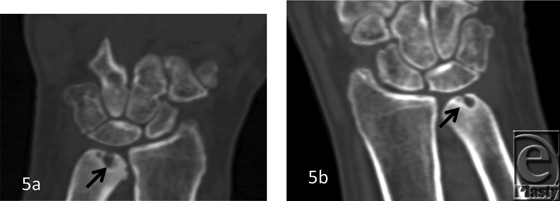

The patient demographics, clinical findings, X-ray, and 4D CT imaging findings as well as final patient disposition are depicted in Table 1. All subjects were successfully scanned in various wrist motions (Patient 1-4 videos). 4D CT image quality was adequate in all subjects, and carpal kinematic behavior was easily assessed in various wrist motions both before and after surgical repair. The normal postoperative (Patient 1-3 videos) and altered carpal kinematic behaviors (Patient 4 videos) correlated well with the clinical findings. In the operated wrists (Figs 2-4), while X-rays demonstrated slight gaping after scapholunate ligament repair, kinematic imaging demonstrated no abnormal widening with dynamic motion and showed normal dorsally hinged scissoring type scapholunate motion with motion. However, normal mid-carpal initiated wrist motion on flexion/extension was replaced by radiocarpal initiated motion, likely because of midcarpal stiffness/scarring. Clinical suspicion of ulnocarpal abutment was also confirmed in both wrists of Patient 4 (Fig 5).

Patient 4, Videos 1-3: Right wrist. Video 1. Radioulnar maneuver: Ulnocarpal abutment evident on radial deviation position.[Click Here to view video] |

Video 3. Clenched fist maneuver: No abnormal scapholunate widening. Ulnocarpal abutment seen on relaxed phase disappears on clenched fist.[Click Here to view video] |

Patient 4, Videos 4-6: Left wrist. Video 1. Radioulnar maneuver: Ulnocarpal abutment evident on radial deviation position.[Click Here to view video] |